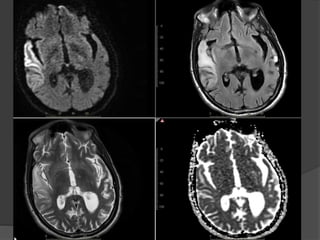

Case 5:17M, Status post cardiac arrest:

July 22

July 16

Bilateral parietal white matter diffusion restriction

and ADC hypointensity

Case 5 Diagnosis: Postanoxic leukoencephalopathy

•Uncommon syndrome (2-3%)of delayed white

matter injury after a hypoxic-ischemic injury, most

commonly due to carbon monoxide intoxication

•Period of relative clinical stability or

improvement, then acute neurologic decline,

typically 2-3 weeks after the initial insult

•DWI and conventional MRI immediately

following the insult may be normal, but reveal

confluent areas of restricted diffusion in the

cerebral white matter later

•Imaging helps in diagnosis and case

management in the acute setting and provides

information about long term prognosis

RadioGraphics 2008. Hypoxic-ischemic brain injury:Imaging findings from birth to adulthood